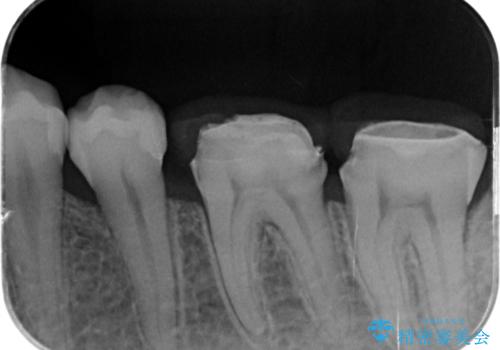

銀歯を外して被せ物の予定でしたが歯の高さが低く取れやすい被せ物になってしまうため歯の高さを変える手術を行いました。

まずはメタルを全て外し仮歯にして、手前のメタルインレーは手術前にセラミックインレーの治療を行いました。

- APF 16.5万円 セラミックインレー 7.7万円×2費用は治療当時の料金となります